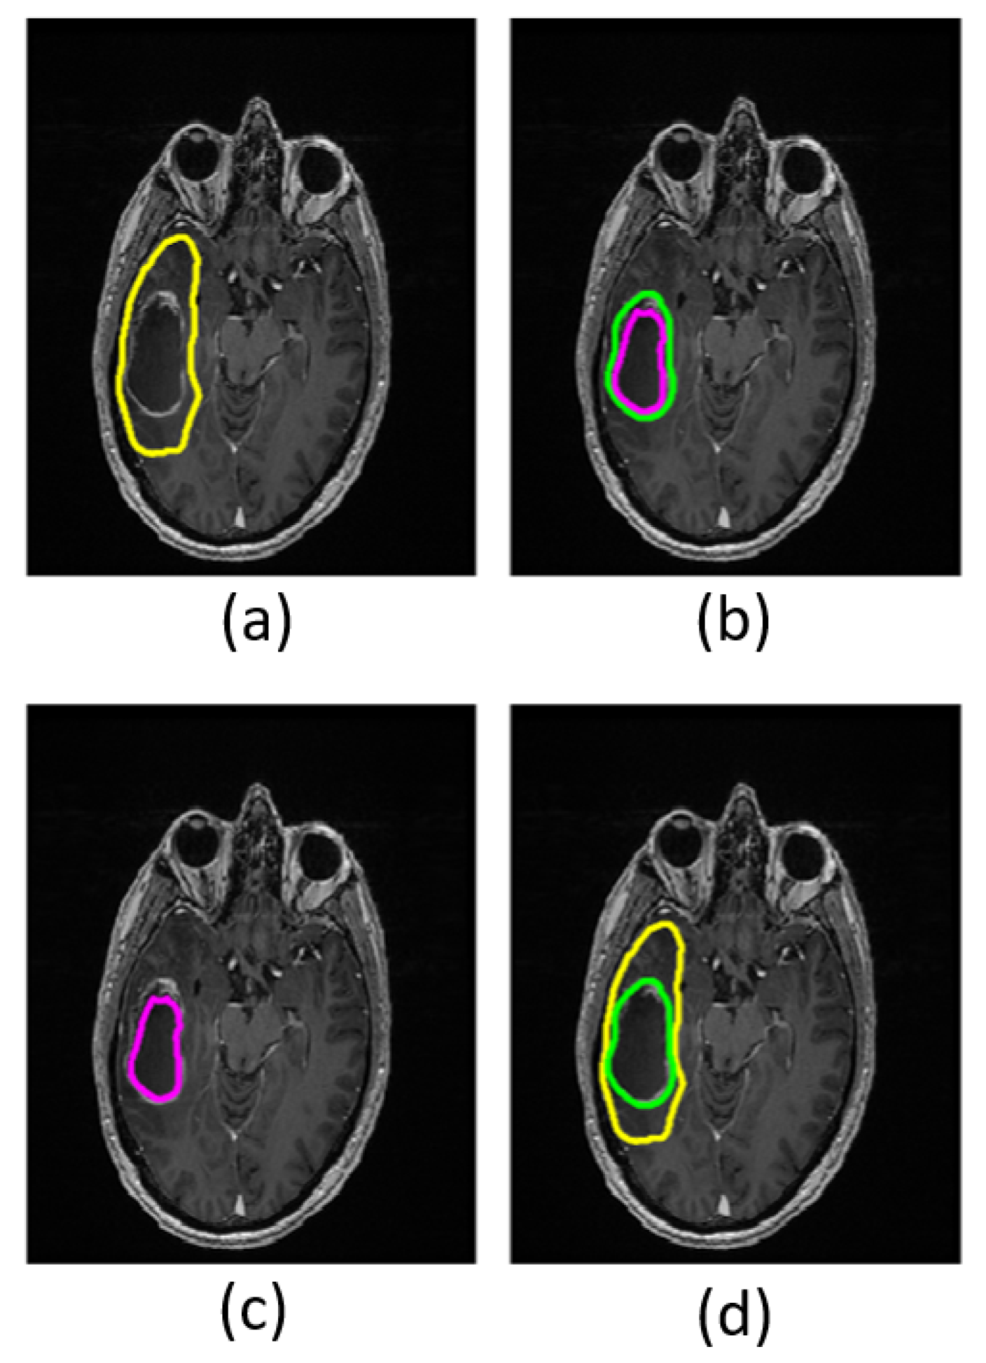

FW elimination increases FA entropy (p ≤ 0.003) and decreases FA skewness (p ≤ 0.004) in the non-enhancing regions in both low- and high-grade tumors (Table 3). Kurtosis does not decrease significantly in low-grade tumors (p = 0.90) but does decrease significantly in high-grade tumors (p ≤ 0.001). The FA distribution shifts toward higher FA values after FW correction. Refer to the Supplementary Material for a complete table of summary variables (Supplementary Material, Table S1). Maps calculated with and without FW correction are shown for a single patient in Figure 5.

Figure 5. Images and maps from a grade IV patient: (a) T1w image; (b) T2w image; (c) free-water (FW)-corrected fractional anisotropy (FAt) map; (d) non-corrected fractional anisotropy (FA) map with contours defining non-enhancing tumor; and (e) FW map. Within the non-enhancing region, more heterogeneity is revealed in the FAt map compared to the FA map. The FW map quantitatively highlights FW content.